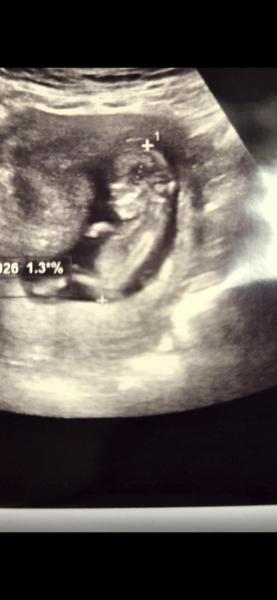

Hallo ihr lieben..   Es ist bis jetzt eine aufregende Reise mit Höhen und Tiefen.     Jetzt durfte ich am Freitag mein Wunder sehen .und lese oftmals was von NuB Therapie.   Mich würde mal einfach interessieren, ob jemand dahin Ahnung hat .    Schönen Abend

Bild zu NUB THERAPIE - Forum für Juni - Mamis